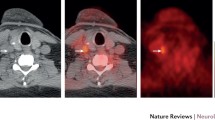

18F-sodium fluoride (18F-NaF): Calcification is the final outcome of inflammation, and one of the key features of atherosclerosis. Microcalcification primarily occurs in the fibrous cap overlying the plaque surface, and contributes significantly to plaque vulnerability. 18F-NaF is a specific tracer commonly used to detect bone metastases. Studies have shown that 18F-NaF can be taken up by atherosclerotic vessel walls, and is associated with the risk factors of atherosclerosis. Other studies have found that 18F-NaF uptake is significantly higher in vulnerable carotid plaques than in contralateral asymptomatic plaques and the control group. The study by Li et al. demonstrated that 18F-NaF PET/CT was useful in the detection of microcalcification activity in carotid atherosclerosis, and can assess the stability of carotid plaques, while low-dose CT can help to determine the degree of plaque calcification and plaque localization (Fig. 12.20).

Comparative study of 18F-FDG PET/CT and 18F-NaF PET/CT in carotid atherosclerosis progression. Transverse 18F-NaF-PET/CT scan of myeloma patients with varying degrees of carotid artery calcification. In non-calcified lesions, the location of 18F-NaF uptake in the carotid plaque was consistent with that of 18F-FDG, and both showing increased calcium uptake (a). In mildly calcified lesions, after progressive arterial calcium accumulation, 18F-NaF uptake showed significant increases from baseline to follow-up (b). In severely calcified lesions, dense calcium components can be observed (c). Arrows indicate calcified lesions